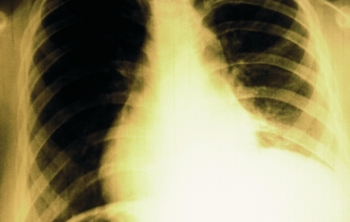

Всемирная Организация здравоохранения продолжает публиковать довольно неутешительные данные, которые на этот раз касаются заболевания туберкулезом.

В прошлом году почти девять миллионов людей заразились этой страшной болезнью, а полтора миллиона от нее скончались.

Правда, есть и некоторые утешающие данные, смертность от заболевания упала за последние 25 лет в полтора раза, и продолжает стабильно падать на полтора процента в год, что связано с тем, что лечение стало гораздо более прогрессивным.

Так, за последние четырнадцать лет были спасены 37 миллионов человек, и произошло это во многом благодаря тщательной диагностике заболевания и эффективному лечению. Однако, серьезной проблемой остается то, что многие не знают о своем диагнозе.